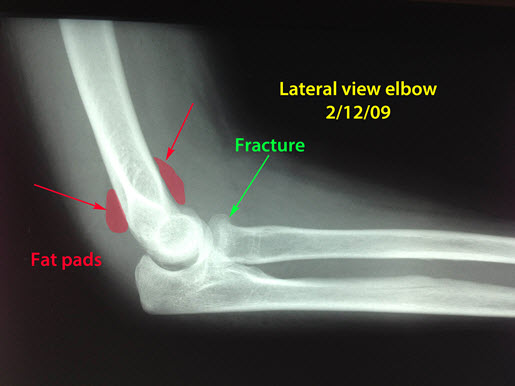

Pertinent images must be isolated and presented in a manner that can be grasped by lay jurors with no understanding of the technology, or frame of reference to the spectrum of normal and abnormal. This can be facilitated by judicious selection of the relevant images, focusing in on the areas of interest, and color coding and annotating the images (Fig. 1-3).

Fig 3: A subtle fracture of the head of the radius bone in the forearm is present (green arrow). The prominent fat pads (red) are usually seen in the setting of the accompanying elbow effusion, which is another indirect sign that a fracture is present.